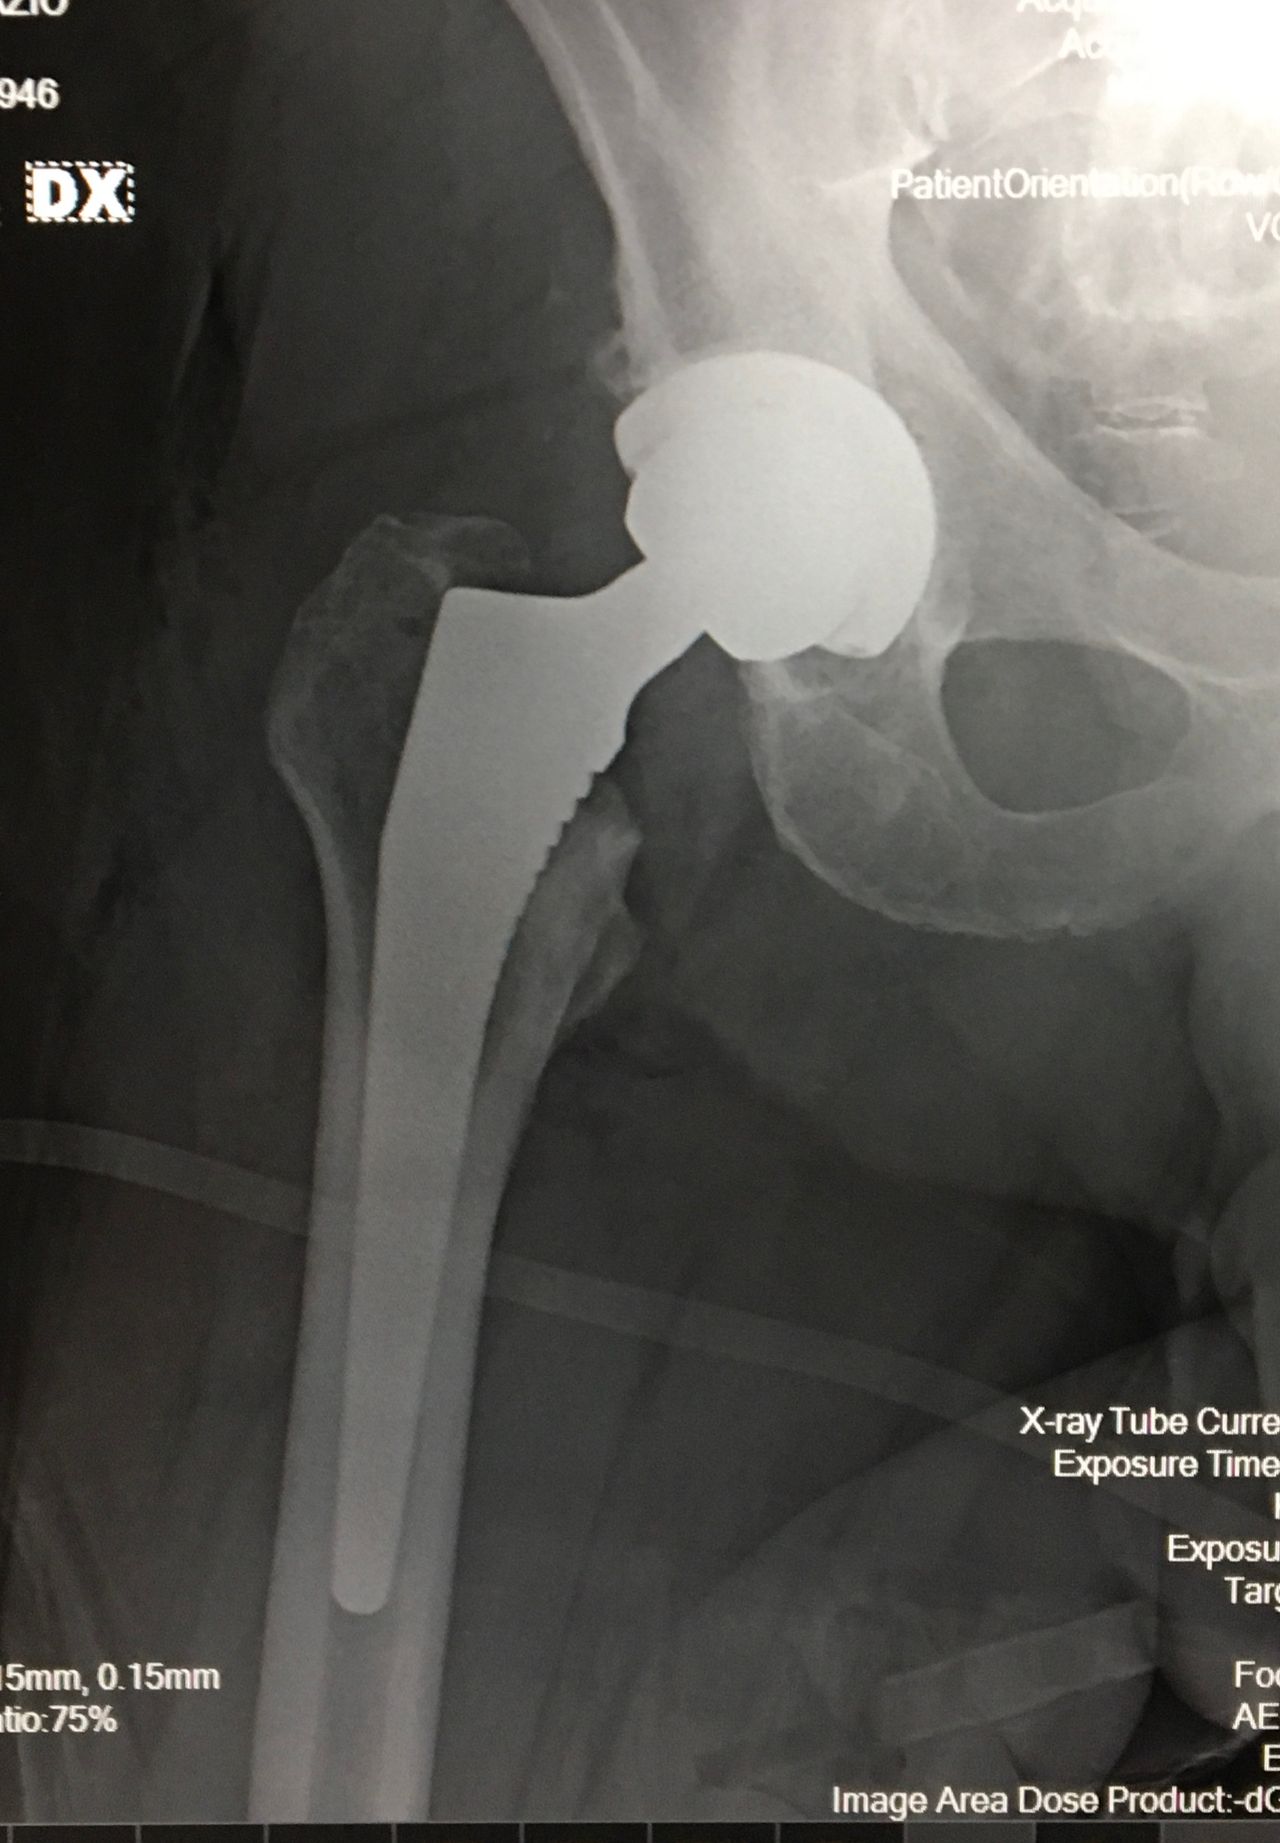

La protesi d’anca

• Ortopedia dell'anca

• Protesi di anca